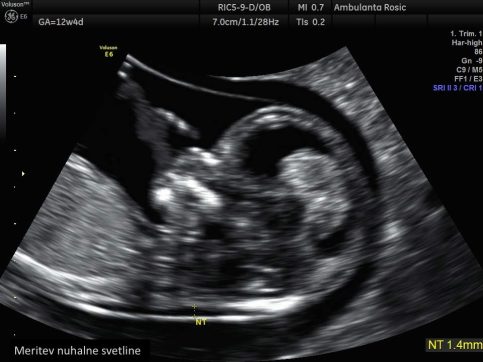

Pri preiskavi z ultrazvokom izmerimo debelino nuhalne svetline na plodovem zatilju. Poleg same meritve debeline nuhalne svetline preiskava zajema tudi meritev velikosti ploda, meritev hitrosti bitja njegovega srca, ugotavljanje prisotnosti nosne kosti in zgodnjo morfologijo ploda, kjer sistematično pregledamo plod in njegov razvoj v prvem trimesečju. Pri izračunu tveganja pa upoštevamo tudi starost nosečnice, saj imajo starejše nosečnice večje tveganje za rojstvo otroka z Downovim sindromom. Širša nuhalna svetlina pomeni večje tveganje za kromosomske nepravilnosti ter druge razvojne nepravilnosti, predvsem srčne napake. Pri velikosti nuhalne svetline nad 3,5 mm je zato svetovan podroben pregled plodovega srca v drugem trimesečju nosečnosti.